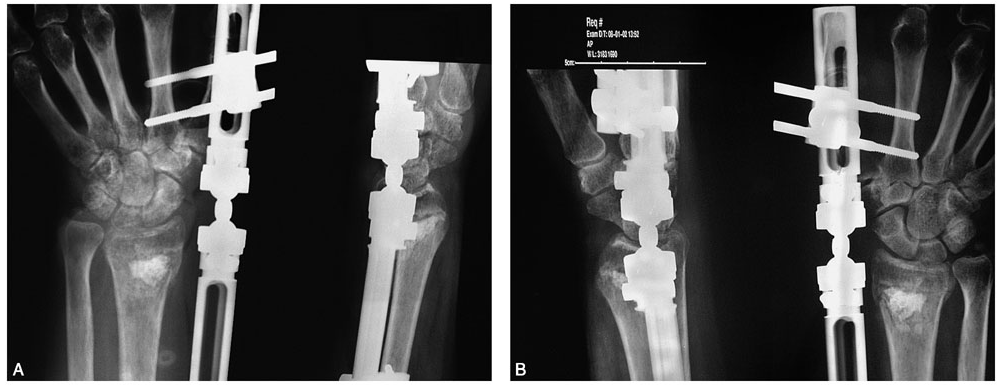

术前拍腕关节正、侧位X线片,腕关节冠状位、矢状位和水平位CT(图2-2)。此患者骨缺损和无法闭合复位的骨片均在背侧,宜采用背侧入路,复位,植骨,固定。取患肢前臂远端桡背侧纵切口(图2-3),从伸拇长肌腱和桡侧伸腕长、短肌之间进入,注意保护血管神经和肌腱,显露清理折端骨缺损区域和背侧移位的骨片(图2-4),复位,植骨,外固定架超关节固定(图2-5、图2-6)。术中透视骨折复位固定满意(图2-7),术后拍X线片证实(图2-8)。此手术的优点在于避免了局部存在内固定物的刺激,避免二期切开取出固定物所致的再次损伤。

图2-5 外固定架超关节固定

图2-6 显示植骨和骨片复位

图2-7 术中透视示骨折复位、固定、植骨满意

图2-8 术后X线片示骨折复位、固定、植骨满意